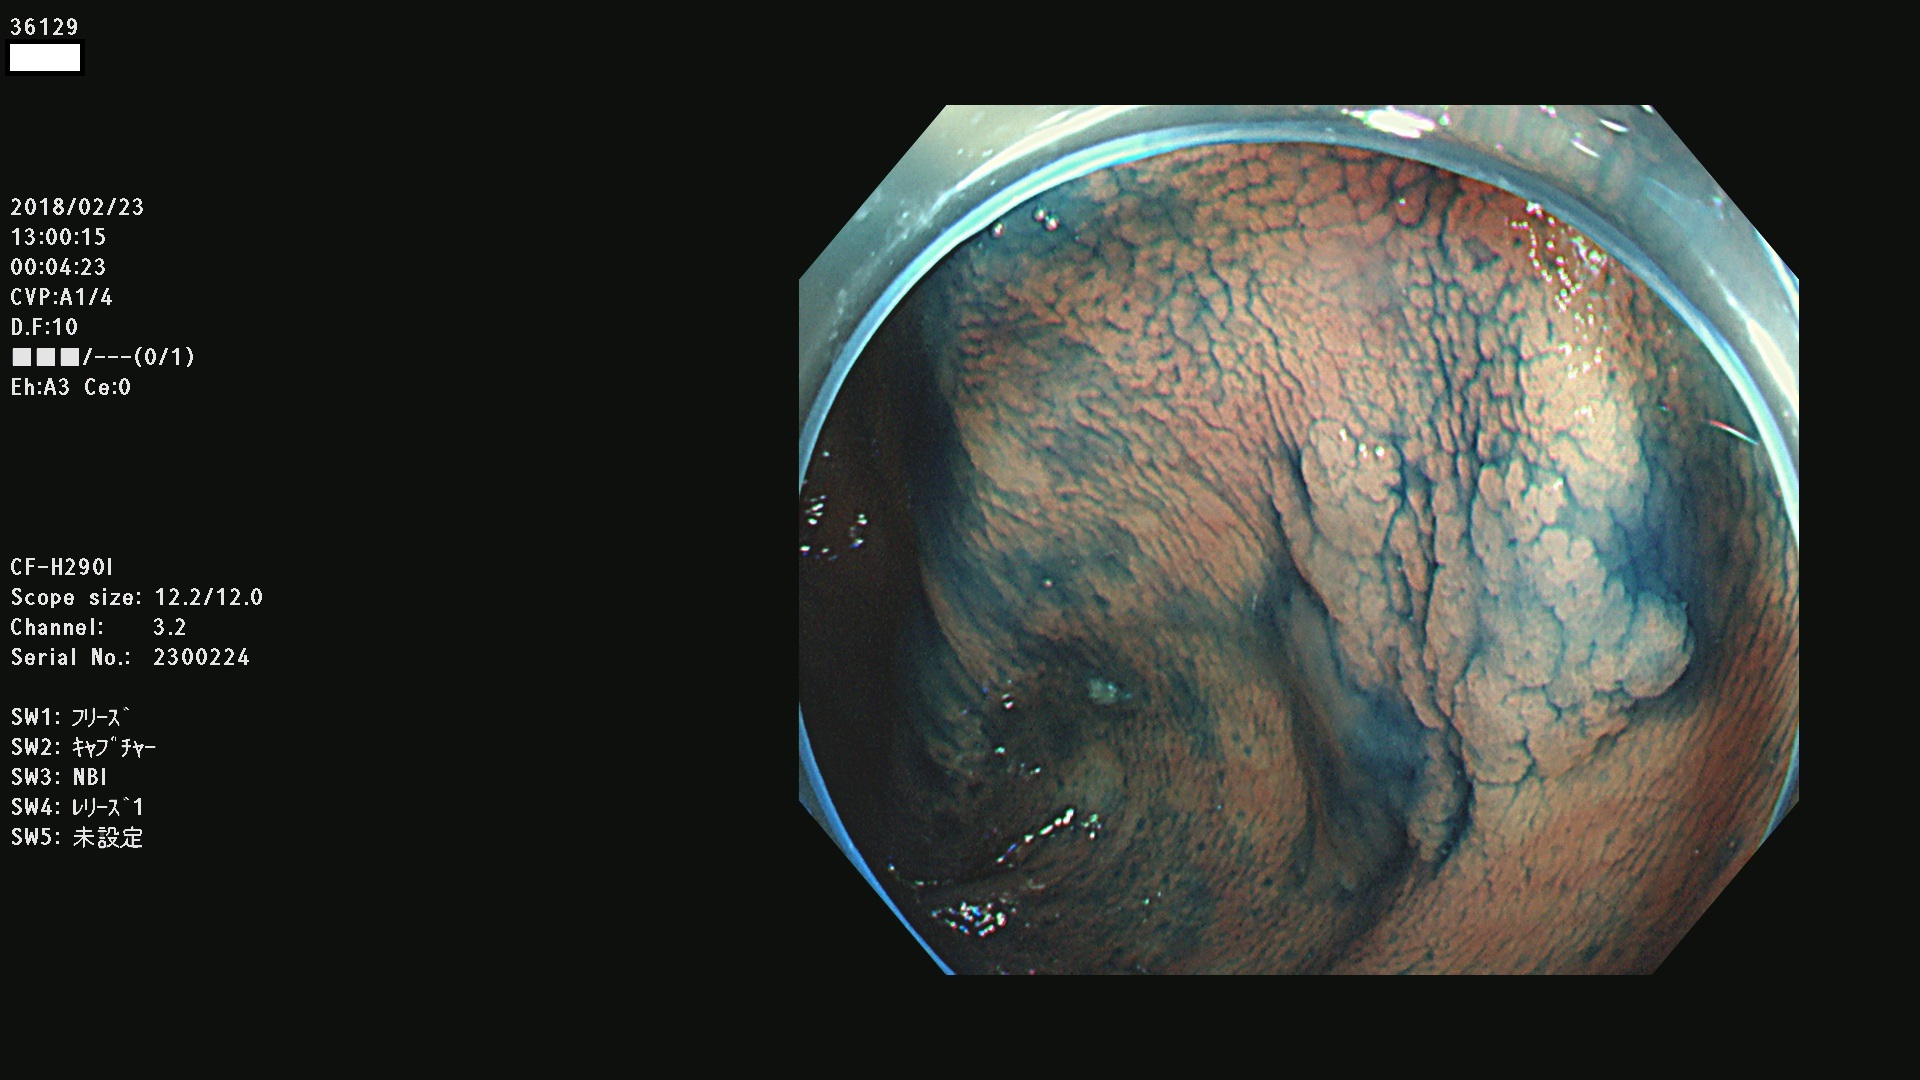

腺腫発見率57 % (カルテ番号 36100〜36199の100名の方の検査結果で集計)大腸癌検診最新情報

以下のカルテ番号の方に腺腫(Adenoma,Group3〜5)が見つかりました(集計法)

36100 36101 36102 36103 36104 36105 36107 36108 36110 36111 36114 36115 36117 36119 36120 36122 36125 36127 36129(SSA/Pのみ) 36133 36135 36137 36138 36139 36143 36144 36146 36147 36152 36153 36154 36155 36157(SSA/Pのみ) 36158 36162 36163 36165 36167 36169 36170 36173 36174 36176 36177 36178 36179 36180 36183 36185 36187 36189 36190(SSA/Pのみ) 36191 36193 36195(SSA/Pのみ) 36197(SSA/Pのみ) 36199(SSA/Pのみ)

発見困難で危険性の高い平坦型病変(上記100名より抽出) ![]()